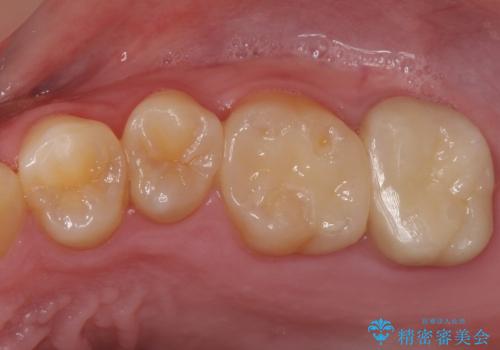

歯の表面に穴が開くほどの虫歯は歯の中でかなり大きくなっていることが多いです。

虫歯の除去後は適合の良い修復物を入れることで今後の虫歯リスクを減らします。